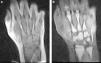

Resonancia magnética periférica: alteración de la señal del hueso con inversión de la misma (médula ósea hiperintensa en T1 e hipointensa en STIR) en ambas manos (fig. 1).

A) Mano derecha, coronal T1, desde radiocubital distal a metacarpofalángicas: hipointensidad de todos los huesos con pequeñas zonas hiperintensas en diáfisis de metacarpianos (2.° y 4.°). Grasa hiperintensa, como corresponde a esta secuencia. B) Mano derecha, coronal STIR, desde radiocubital distal a metacarpofalángicas: hiperintensidad en todos los huesos con pequeñas zonas hipointensas en diáfisis de metacarpianos (2.° y 4.°). Grasa hipointensa, como corresponde a esta secuencia.